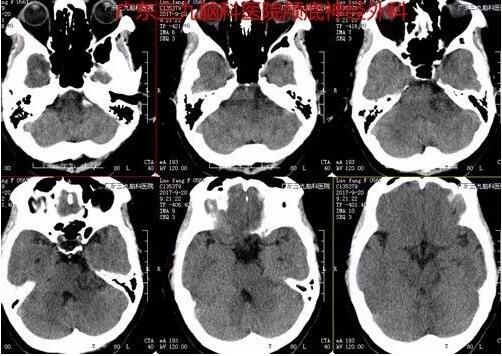

图1:术前CT提示左侧桥小脑角一团块状不均匀低密度影

图2:头颅CTA示:左侧桥小脑角区示一团块状不均匀低密度影,其内示多发细小血管影。双侧大脑前、中、后动脉主干及分支走行规则,未见狭窄、闭塞或畸形血管影。所示双侧颈内动脉、椎动脉及基底动脉形态及密度未见异常